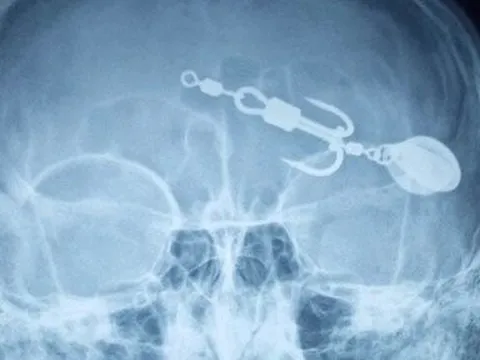

Xem câu cá, bé trai 13 tuổi bị lưỡi câu móc vào mắt

Mới đây, Trung tâm Y tế huyện Thanh Sơn (Phú Thọ) vừa kịp thời cấp cứu bé trai 13 tuổi bị lưỡi câu móc vào mắt.